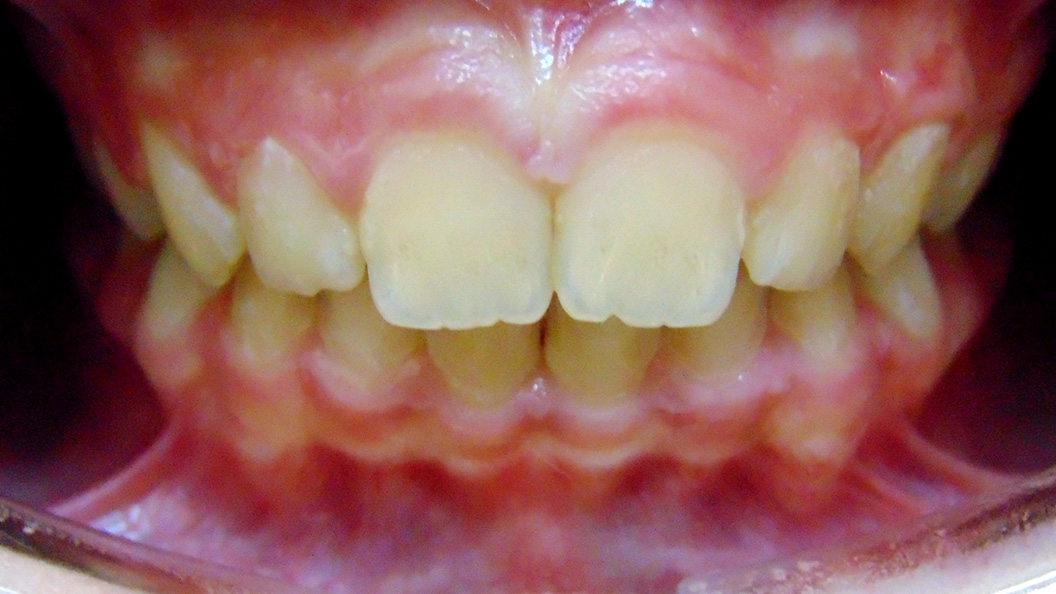

Родители пациента обратились в «Стоматологию Комфорта» для исправления неправильного прикуса у ребёнка 11-и лет. Врач-ортодонт Резниченко Анна Васильевна провела осмотр и установила, что у пациента наблюдается суперпозиция 23 зуба и вертикальная резцовая окклюзия. Врачом было принято решение о целесообразности лечения съёмным аппаратом-ортокорректором Occlus-o-Guide.

Ортокорректор Occlus-o-Guide производства США предотвращает нарушение окклюзии зубных рядов в сменном прикусе. Аппарат ускоряет процесс выравнивания зубных единиц у детей, а также способствует улучшению профиля ребёнка. Occlus-o-Guide предназначен для лечебных ортодонтических упражнений. Его применение направляет и смещает прорезывающиеся постоянные зубы к нормальной окклюзии.